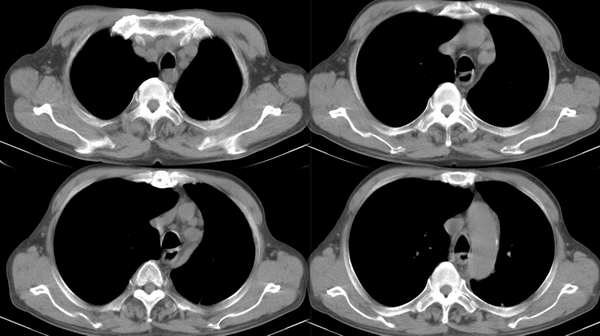

m67y外院ct诊断肺ca,现来我科复查ct

典型中央型肺ca

左主支气管变窄,左下叶部分不张,考虑肺癌可能性大

考虑左下肺中央型肺癌并肺不张,建议支气管镜检查。

主-肺动脉窗似有大的淋巴结,肝也像有多发低密度灶。看不太清,是不是转移?

[emb6]大家的意见。注意肝脏。